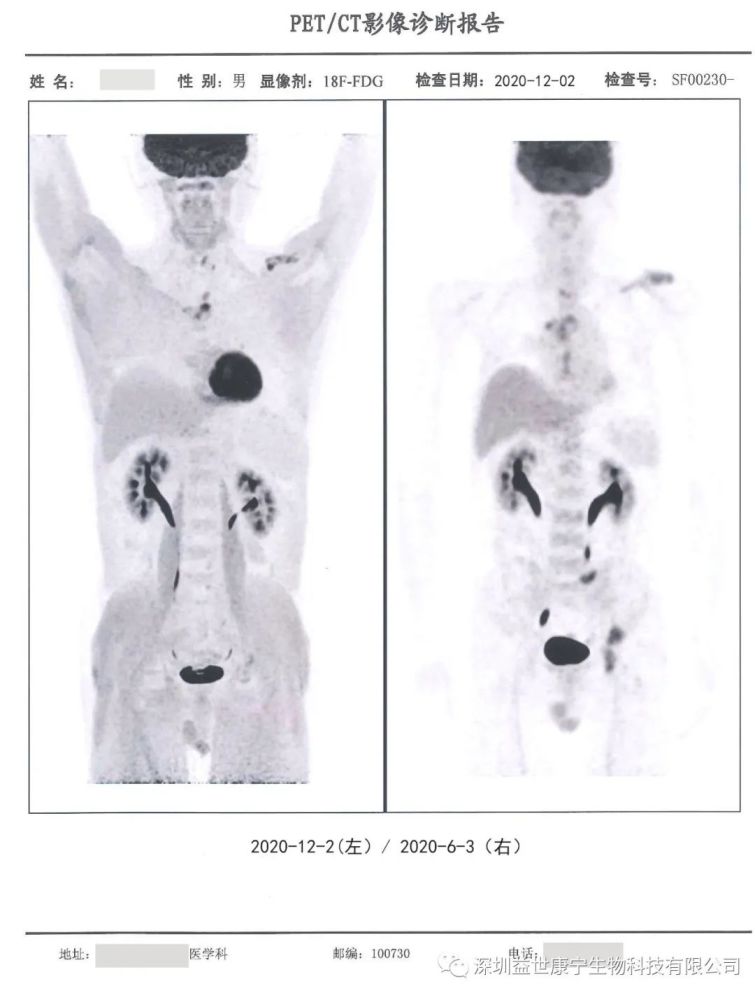

actl细胞联合奥希替尼治疗肺腺癌伴骨转移一例分析

骨转移

骨转移ct

骨转移图片

肺癌骨转移ct图片